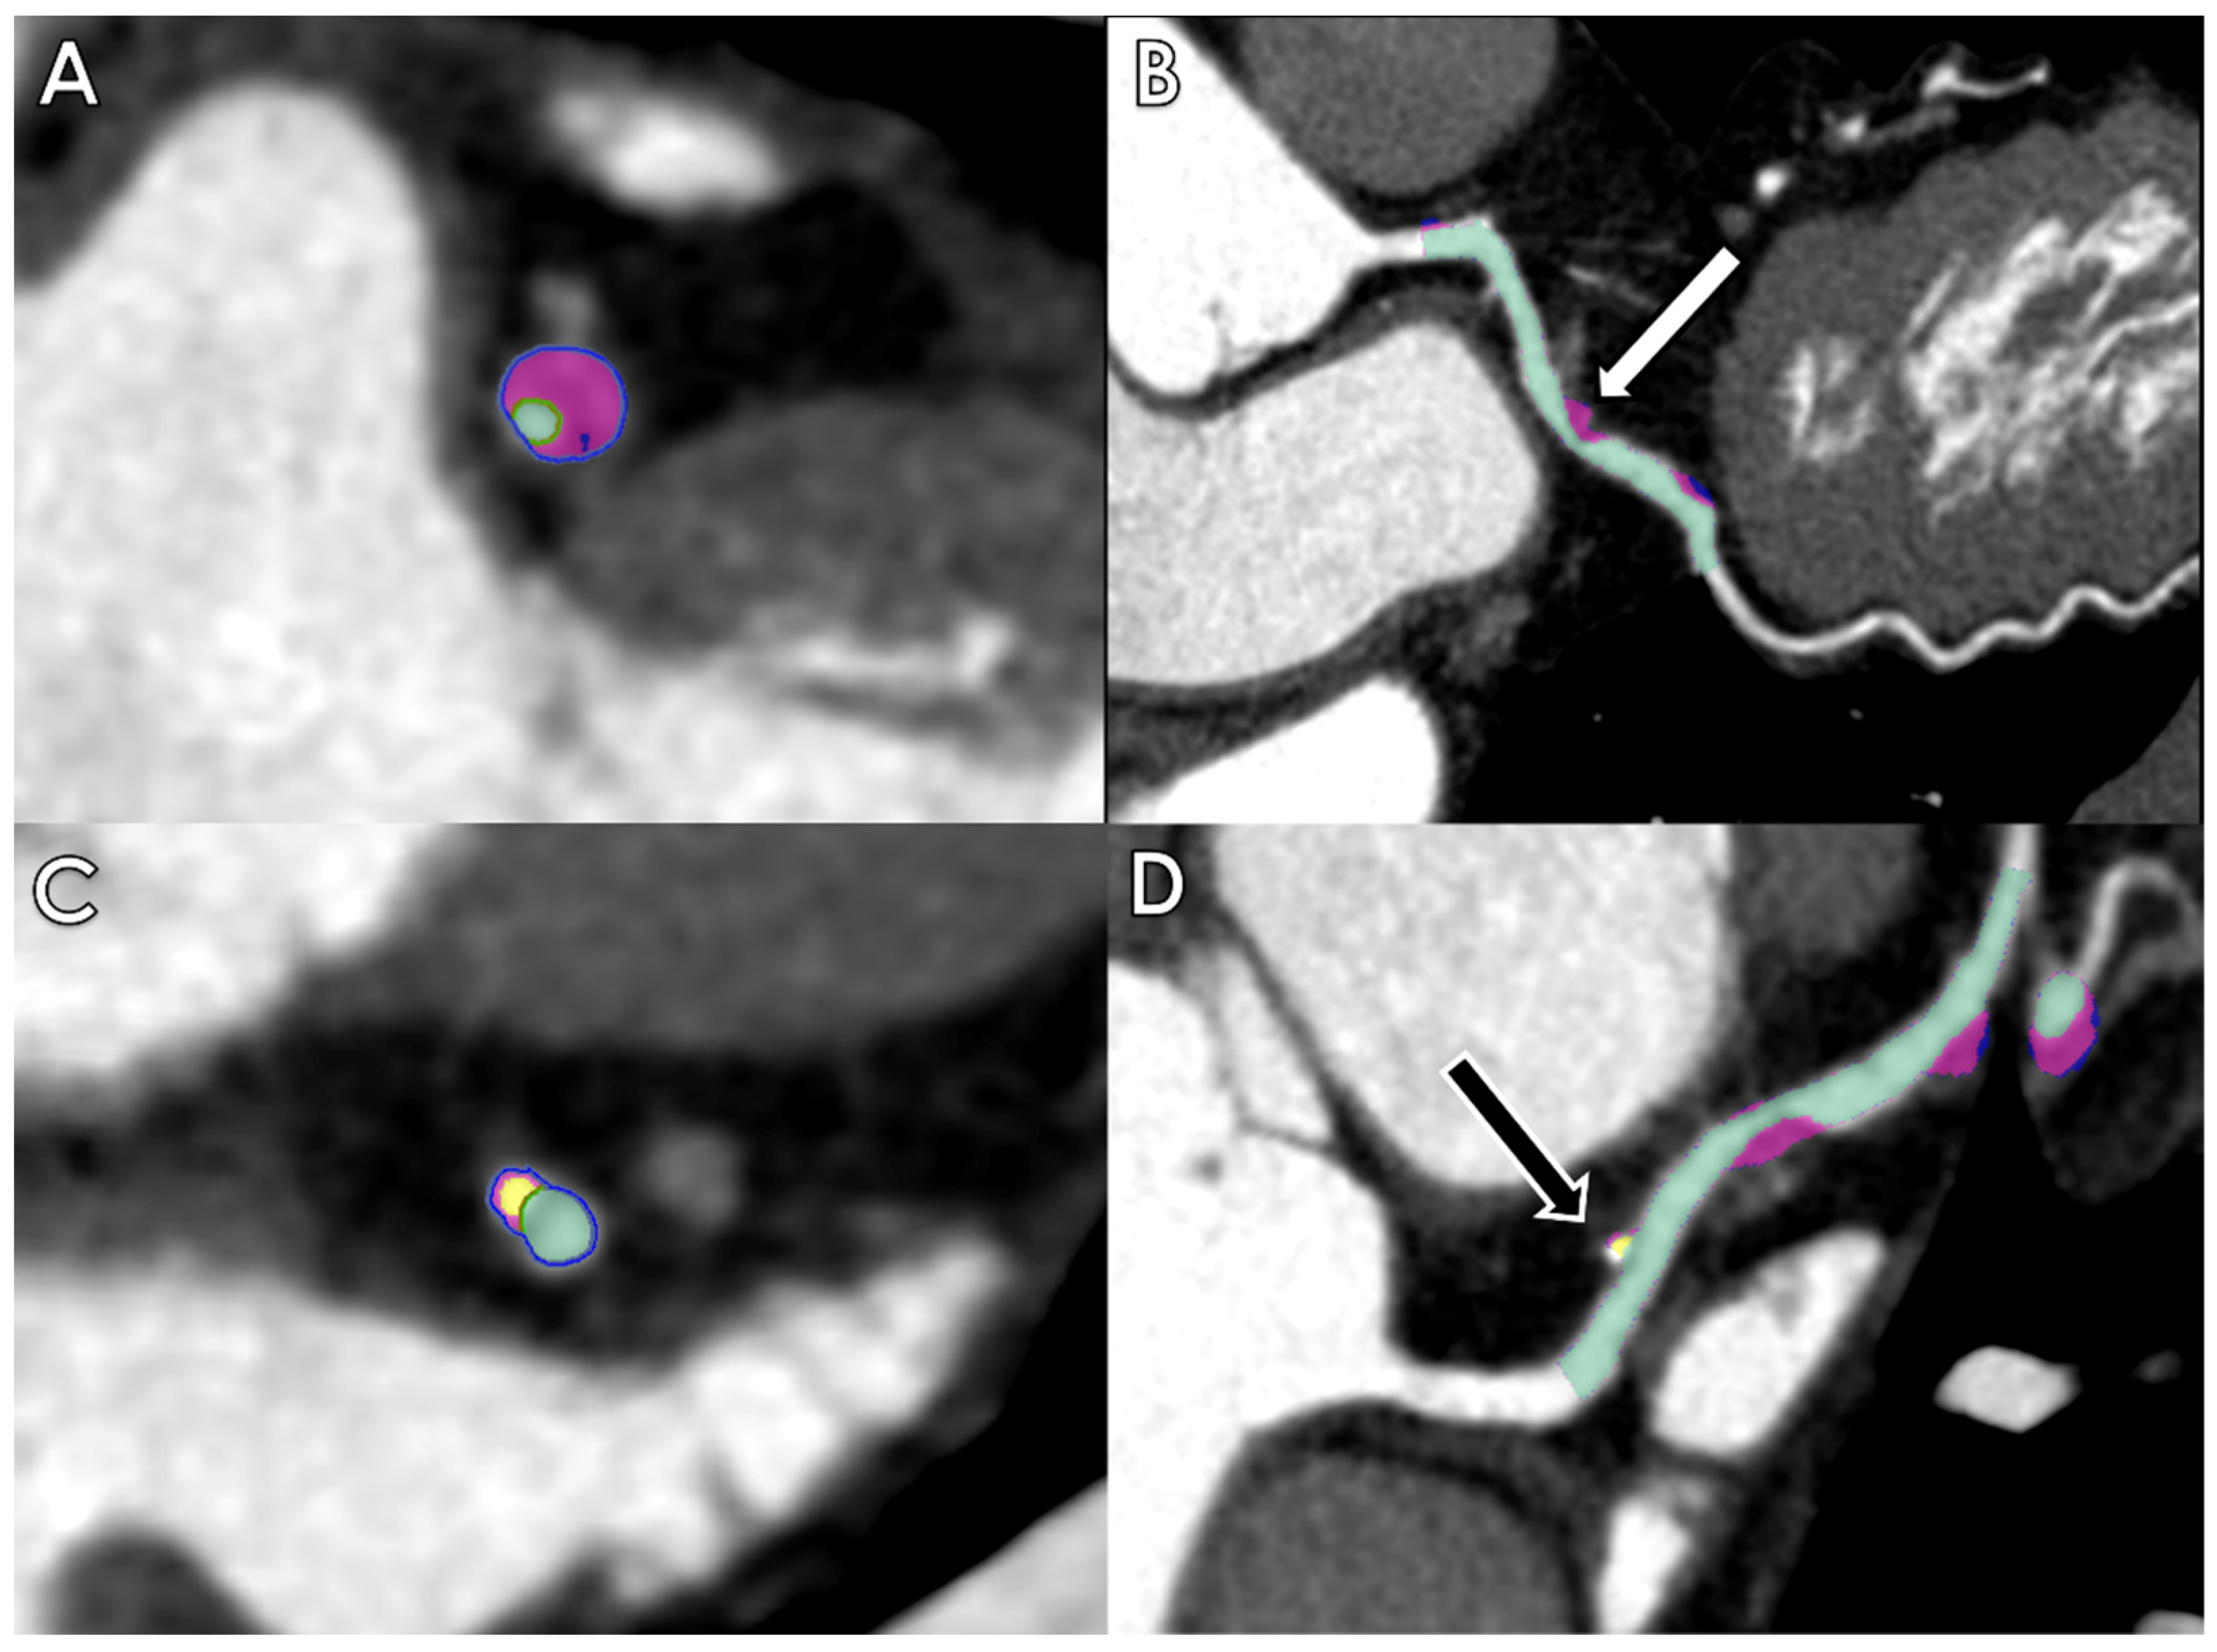

Coronary computed tomography angiography (CCTA) provides excellent visualization of coronary arteries, and its application for the assessment of coronary stenosis and plaque characterization has been widely validated [18,19,20]. AI can be very helpful in the evaluation of these features (Figure 1).

Figure 1.

Axial and multiplanar reconstruction of quantitative plaque AI-based measurements of a fibrofatty plaque with positive remodelling determining severe stenosis of the left descending artery (LAD) ((A,B)—white arrow) and of a calcified plaque determining mild stenosis of the LAD ((C,D)—black arrow).

Nonetheless, post-processing and image evaluation can be very time-consuming and susceptible to inter-observer variability, which may be reduced by AI-based algorithms.